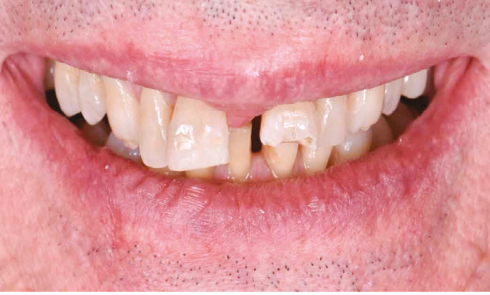

Article réservé à nos abonnés Restauration directe au composite : permettre de garder le naturel en l’harmonisant

3es lauréats du grand prix Id : Utilisation des techniques de collage en omnipratique 2020 avec le soutien institutionnel de...